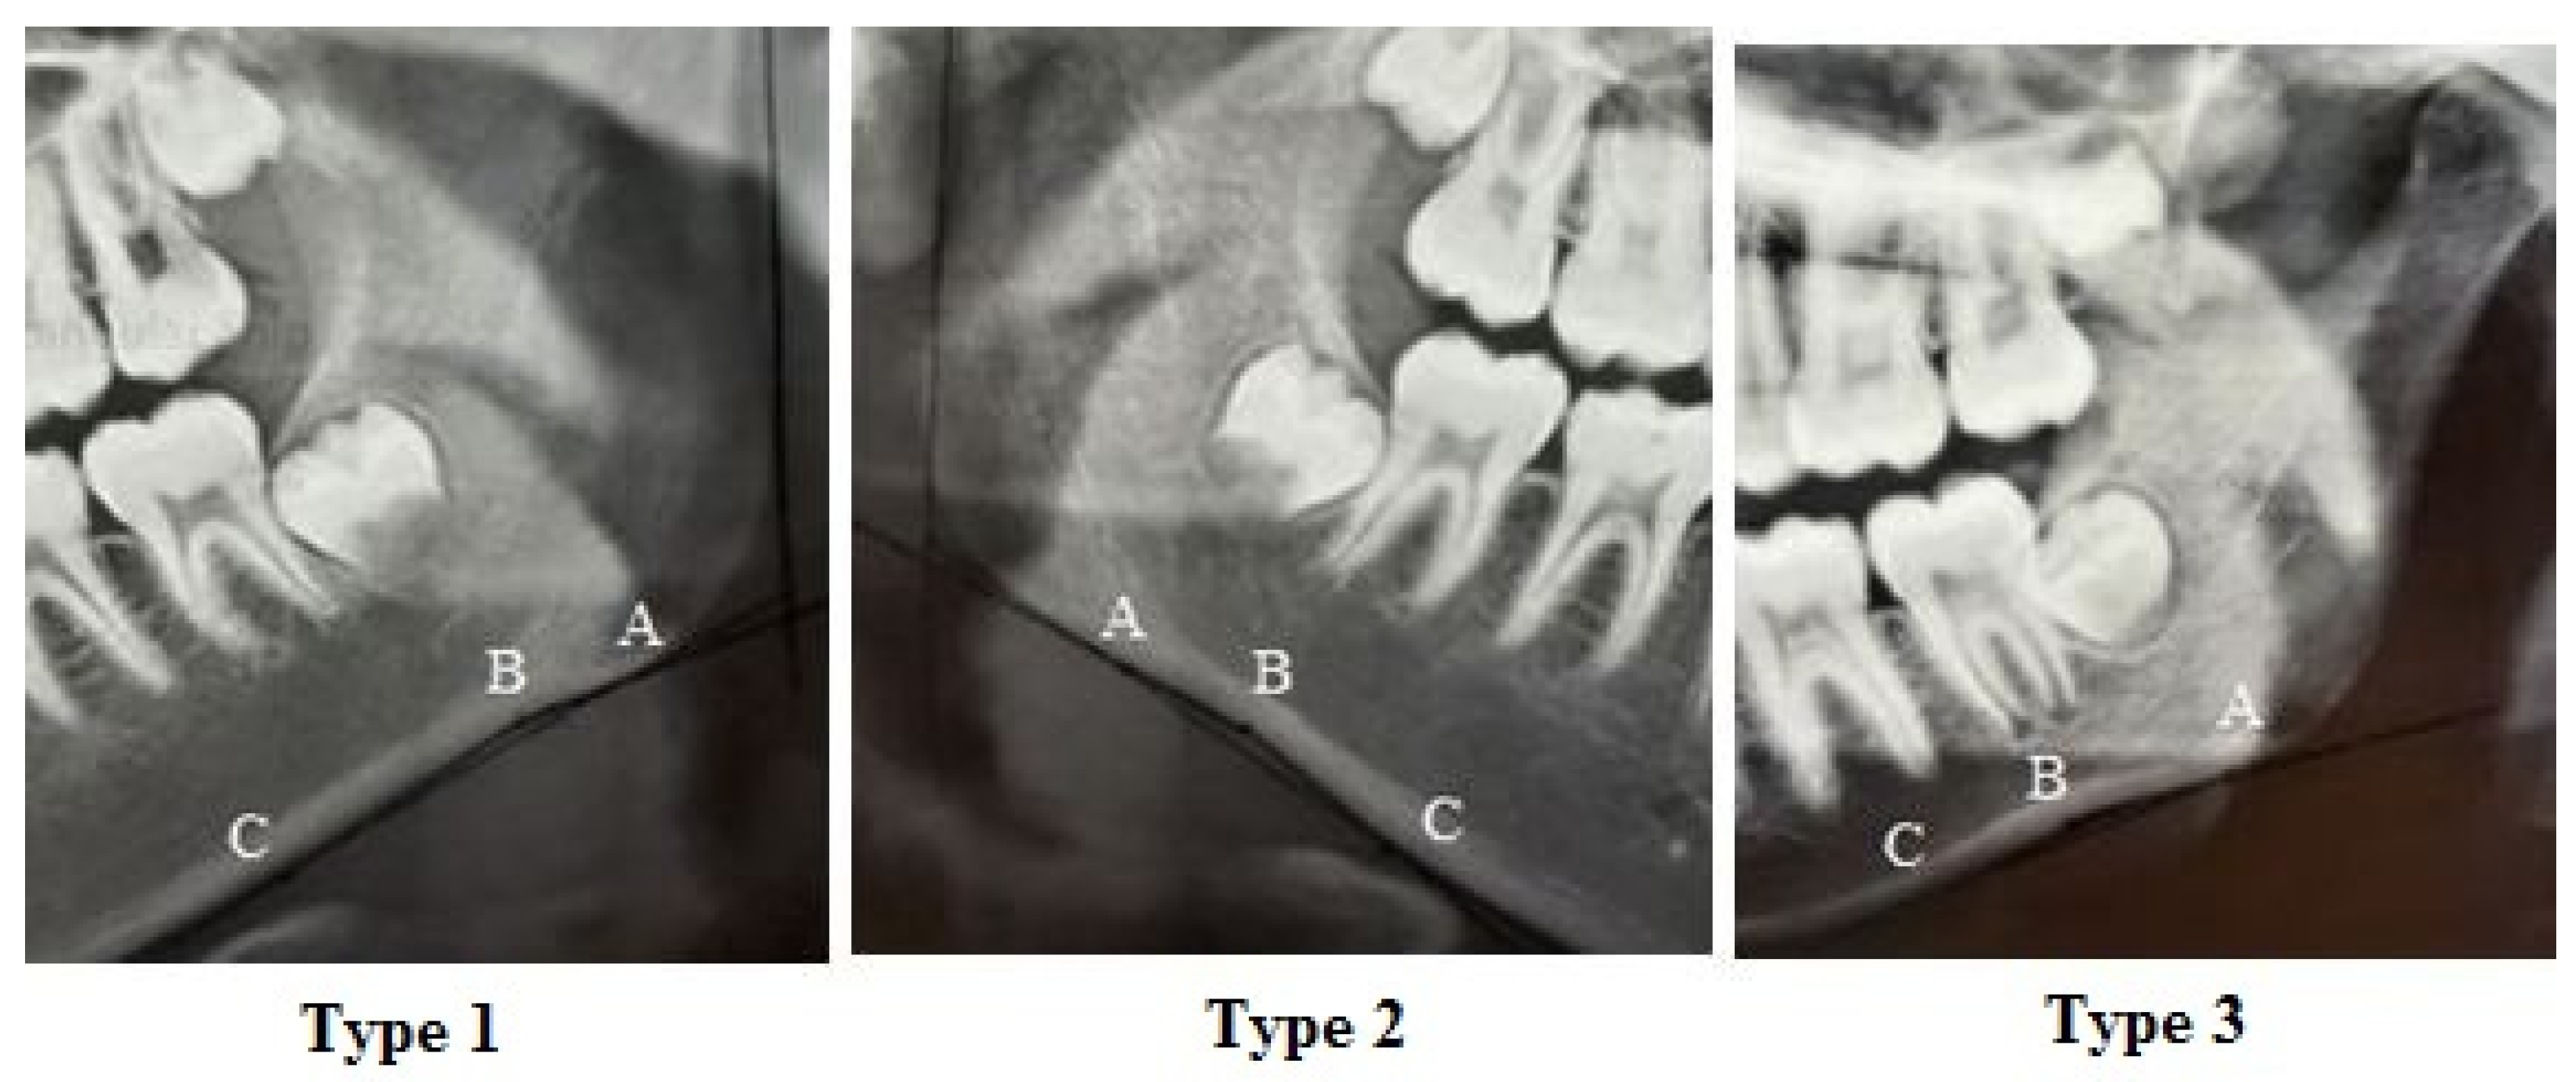

- Porwolik, M.; Porwolik, K.; Domagała, Z.A.; Woźniak, S.; Dąbrowski, P.; Kacała, R.; Kordecki, H.; Chmielewski, P.; Abu Faraj, S.; Gworys, B. Typology of the antegonial notch in the human mandible. Folia Morphol. 2015, 74, 365–371. [Google Scholar] [CrossRef]

| Right antegonial notch type | Class I | 92 | 52.9 |

| Class II | 76 | 43.7 | |

| Class III | 6 | 3.4 | |

| Left antegonial notch type | Class I | 114 | 65.5 |

| Class II | 50 | 28.7 | |

| Class III | 10 | 5.7 |